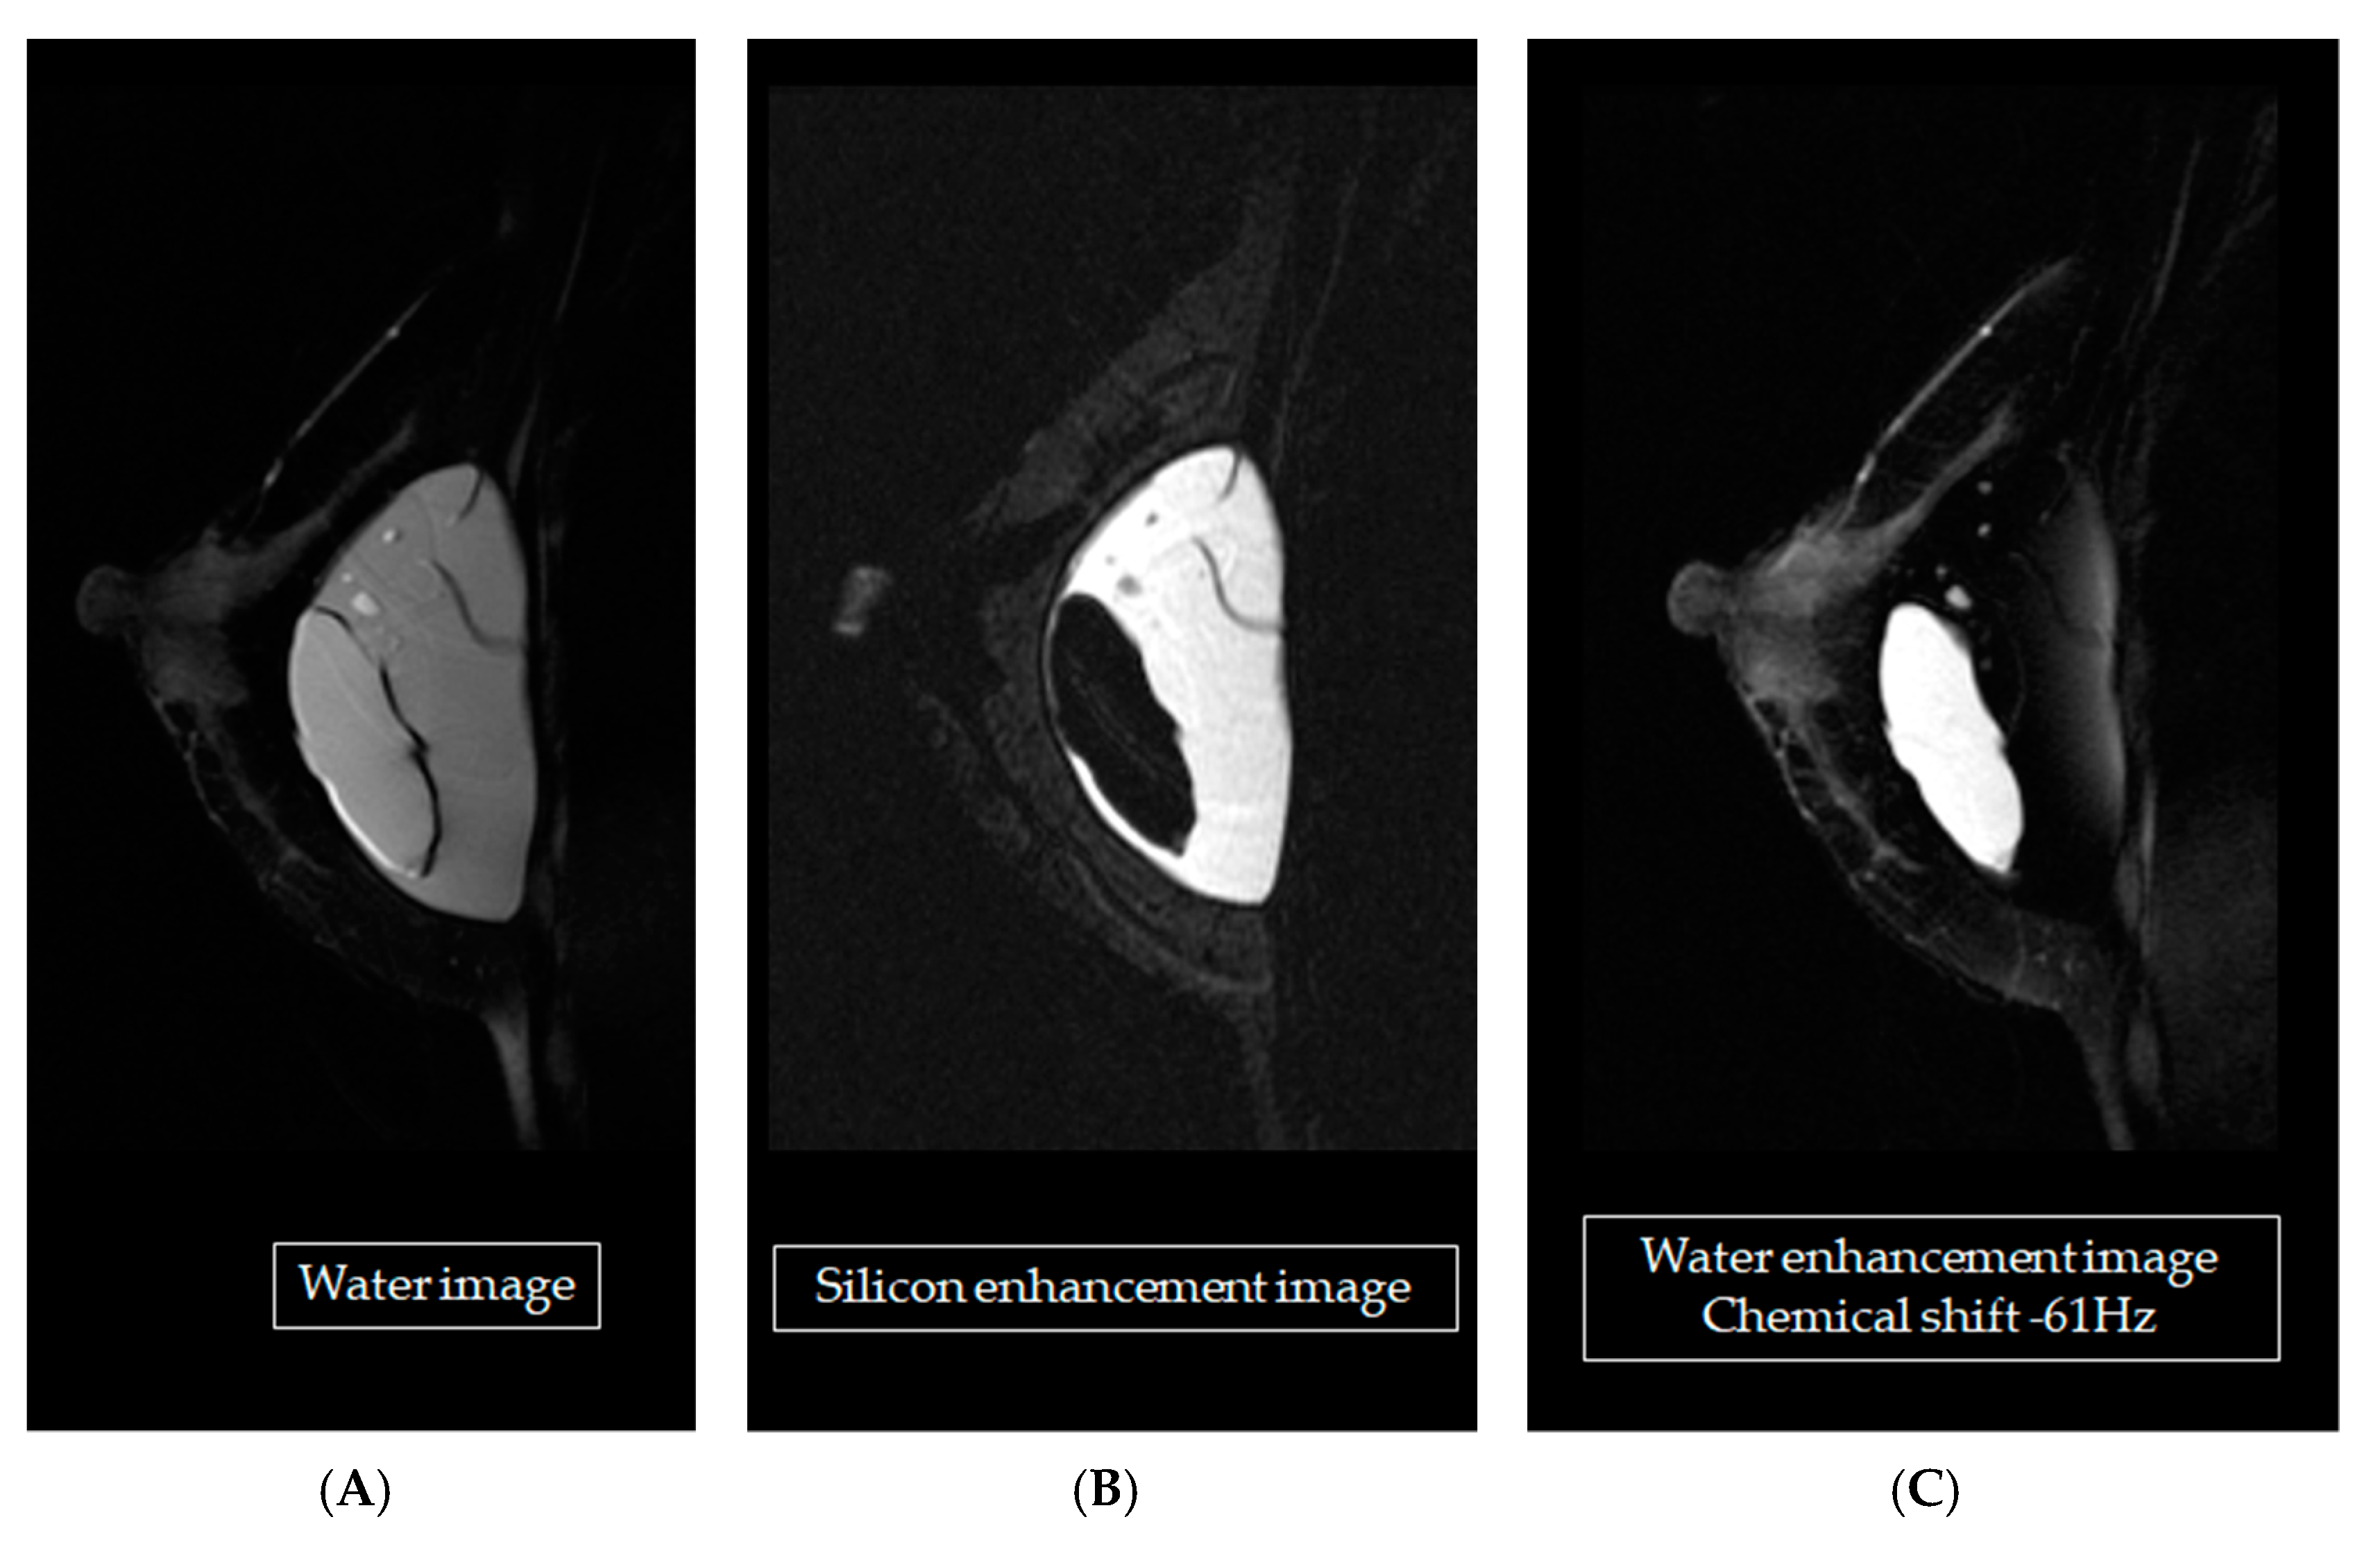

One participant had breast carcinoma proven by her history, 3 silicone implants leaked, and all participants had siliconomas. Figure 2 shows scans of implants made with silicone, oil, or saline.

The T2W FSE technique provided the strongest signal intensity from the saline-bag implant but the weakest from the silicone-bag implant, resulting in the greatest difference between the two. The STIR water-saturation technique also resulted in the greatest difference between the two, but in the opposing direction—it provided the strongest signal intensity from the silicone-bag implant and the weakest from the saline-bag implant. Breast cancer was distinguishable only when dynamic contrast enhancement was added. Signal intensity from cancerous tissue was rated “+++”, whereas those from mammary glands and saline-bag implants were rated “+”. The rating of “-” given to silicone was also relatively high in contrast, as shown in Figure 3.

Figure 2. The MR images of three implants, one each of silicone, oil, and saline, using four MRI pulse sequences: (A) T1-weighted (T1W); (B) T2-weighted (T2W); (C) T2W fat-saturation; and (D) short-tau inversion recovery (STIR) water-saturation.